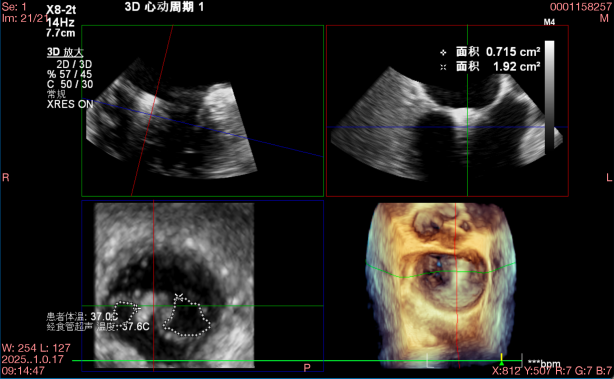

退行性二尖瓣反流(DMR),A2-A3脱垂伴连枷样运动(脱垂范围:17mm,连枷间距:7mm),P3脱垂,反流主要位于2-3区,MR重度4+(VC:6*17 mm),A3:18mm,P3:9mm,A2:24mm,P2:14mm,AP:32mm,二尖瓣口面积MVA约 5.6cm²,左房、左室明显扩大。

术中操作(关键步骤超声)

在全麻下,于心尖入路完成ValveClamp®装置植入。术中多学科团队密切配合,超声全程实时指导操作。最终,于2偏3区成功植入一枚Ⅲf夹子,一次夹合完成。前叶夹合量12mm,后叶夹合量10mm,反流降至1+,导管操作时间30分钟。术后平均跨瓣压差3mmHg。

术前反流 术后反流

术中剪影